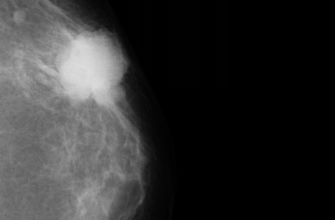

Дерматоскопия — это неинвазивкий метод осмотра кожных образований с использованием специального прибора, дерматоскопа. Этот прибор позволяет максимально подробно рассмотреть структуру и цветовые особенности кожных структур, что значительно повышает точность диагностики различных заболеваний, особенно меланомы и других злокачественных новообразований.

- Высокая точность и надежность диагностики, современные алгоритмы способны обнаруживать меланомы и другие кожные заболевания с точностью, не уступающей опытным специалистам.

Для работы систем ИИ применяются различные модели машинного обучения и глубокого обучения. Наиболее популярными являются сверточные нейронные сети (Convolutional Neural Networks, CNN), которые отлично справляются с анализом изображений.

Обучение таких систем происходит на больших наборах аннотированных данных, где каждое изображение помечено как доброкачественное или злокачественное, а также содержит описание характеристик. После обучения модель способна самостоятельно распознавать признаки и делать оценки.

Многие клиники и лаборатории уже успешно применяют системы ИИ для дерматоскопии. Например, крупные медицинские центры внедрили автоматические скрининговые системы, которые позволяют значительно ускорить поток пациентов и повысить точность диагностики. В некоторых случаях, системы показывают точность совпадений с диагнозом опытного дерматолога более чем 90%, что считается отличным результатом.